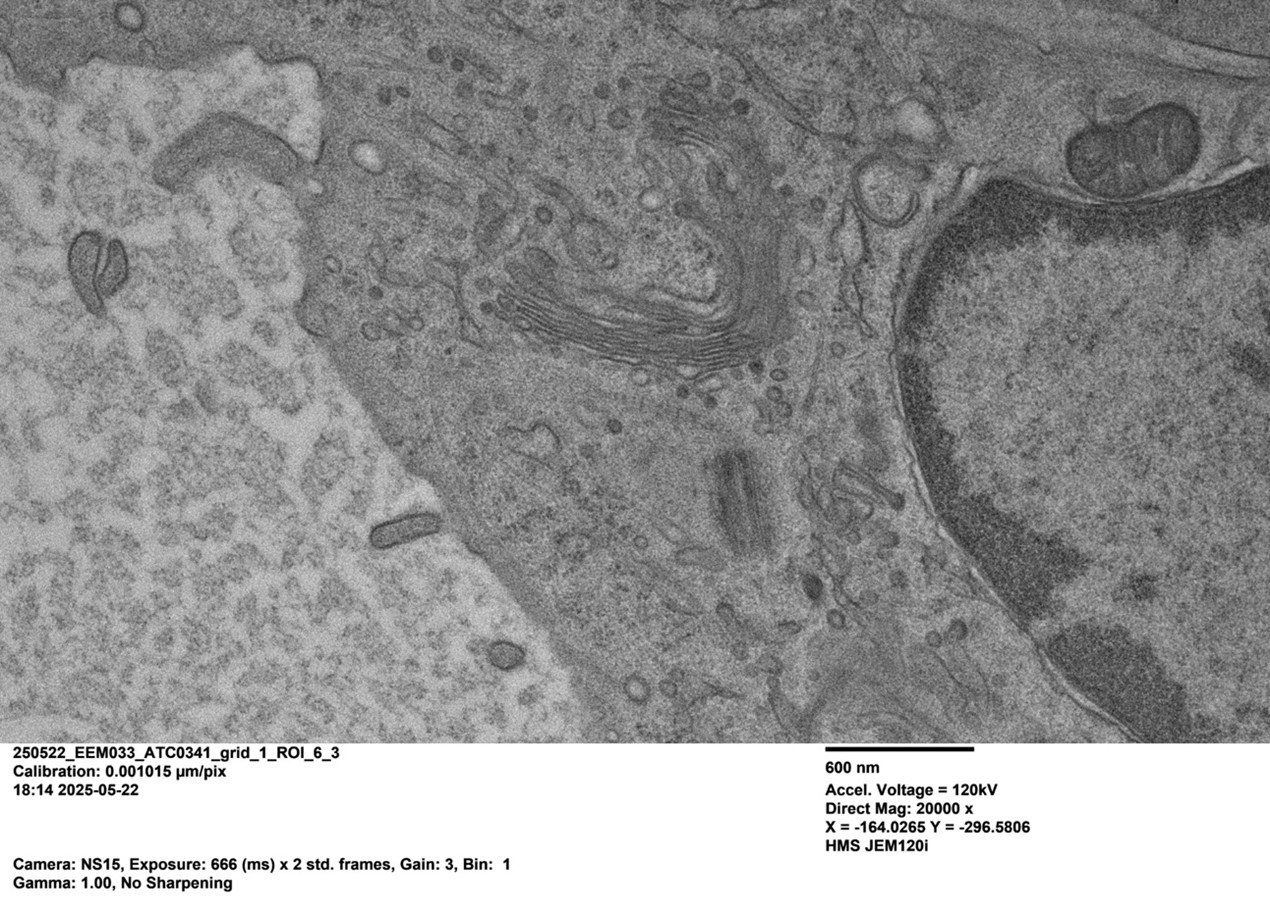

Albert’s cryopreserved brain endothelial cell, imaged with the JEM-120i

Pictured: The nucleus, half of the centrosome (one centriole), the Golgi, ER, a mitochondrion, and microtubules

“The JEM-120i enabled us to screen these hundreds of samples in just under a few months,” Albert explains. “Fast sample exchanges, streamlined interface, and software control allows me to quickly survey the quality of a sample in about half the time it would take me on the old scope.” By rapidly identifying the best samples, Albert was able to select the optimal candidates to send for FIB-SEM: “We’re seeing some really interesting features of tight junctions - cell-cell junctions between neighboring endothelial cells which prevent diffusion of molecules from the blood to the brain.”